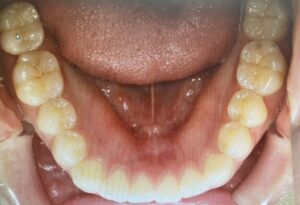

↑被せ物を装着した完成形。

自然な見た目で、問題なく噛める状態です😊

2025年12月1日に来院された時にも経過良好でした✨